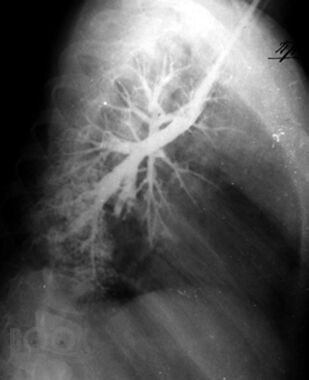

Монография посвящена актуальной проблеме редких (орфанных) заболеваний легких у детей, включающих как собственно наследственные, врожденные, интерстициальные и другие редкие заболевания легких, так и легочные поражения при разнообразной другой редкой патологии. В книге обобщены современные мировые данные, а также многолетний опыт сотрудников клиники пульмонологии Московского НИИ педиатрии и детской хирургии (ныне – НИКИ педиатрии им. акад. Ю.Е. Вельтищева РНИМУ им. Н.И.Пирогова). Для работы над рядом глав привлечены ведущие специалисты из других учреждений страны. Монография адресована детским пульмонологам и аллергологам, практикующим педиатрам и врачам общей практики, другим специалистам, интересущимся орфанной патологией.